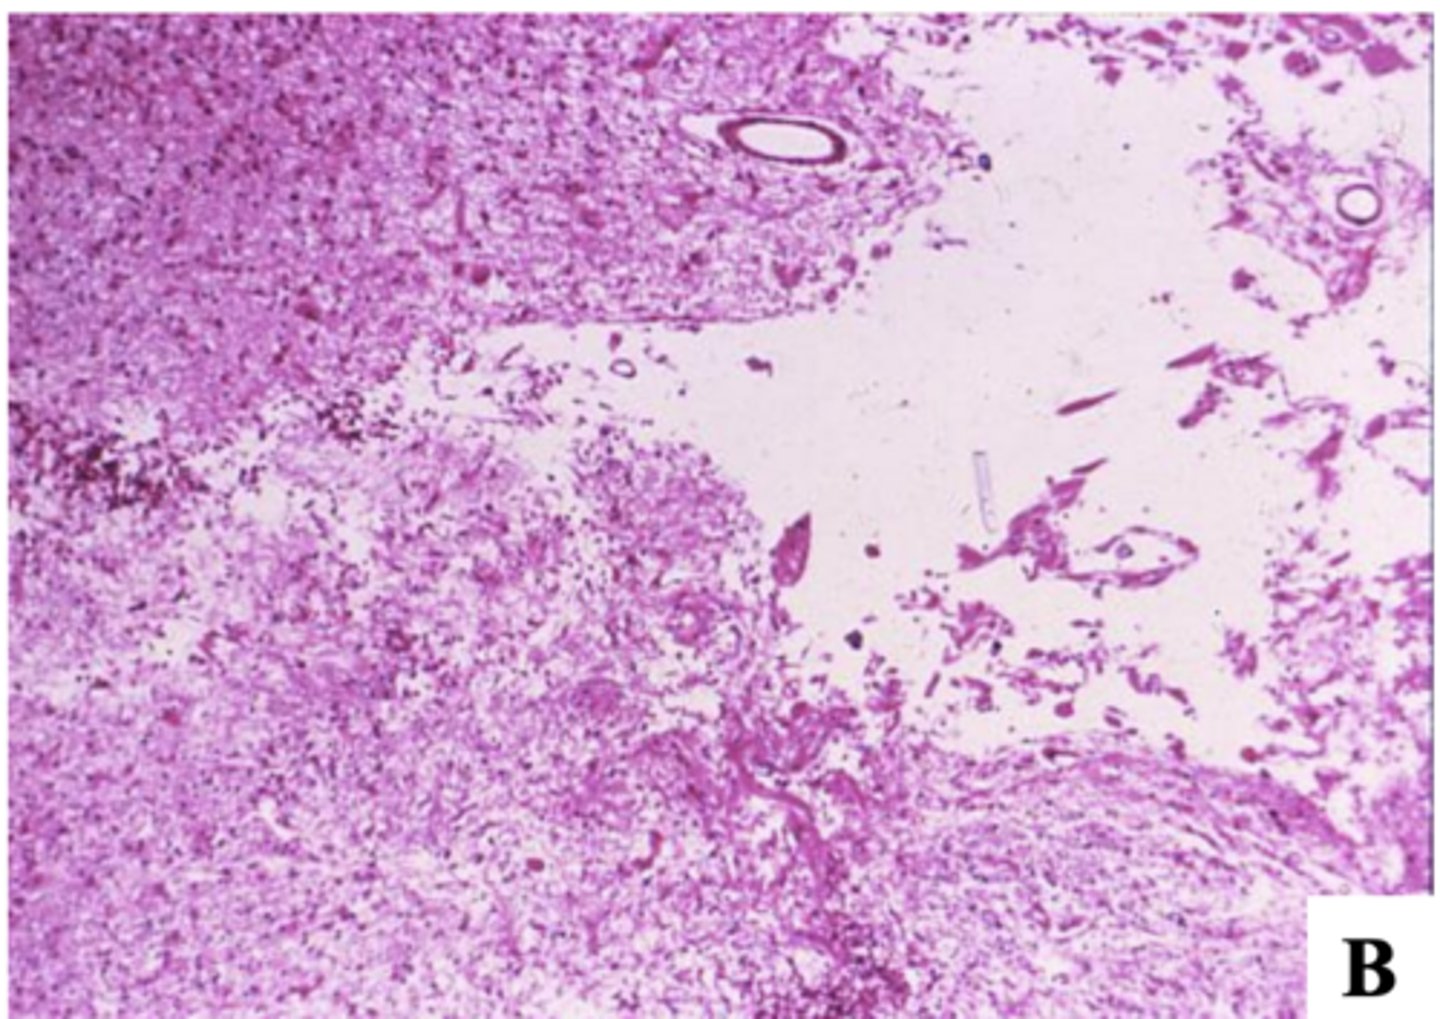

-neuronal dropout

-influx of macrophages (microglial cells -> clean up necrotic debris), fewer lymphocytes and polys

-vascular proliferation

What does the histopathology of an ischemic stroke (infarct) reveal at 4-7 days after the stroke?

4-7 days after the stroke:

-gliosis

-cystic cavity

What does the histopathology of an ischemic stroke (infarct) reveal at 2-3 weeks or months after the stroke?

2-3 weeks or months after the stroke: